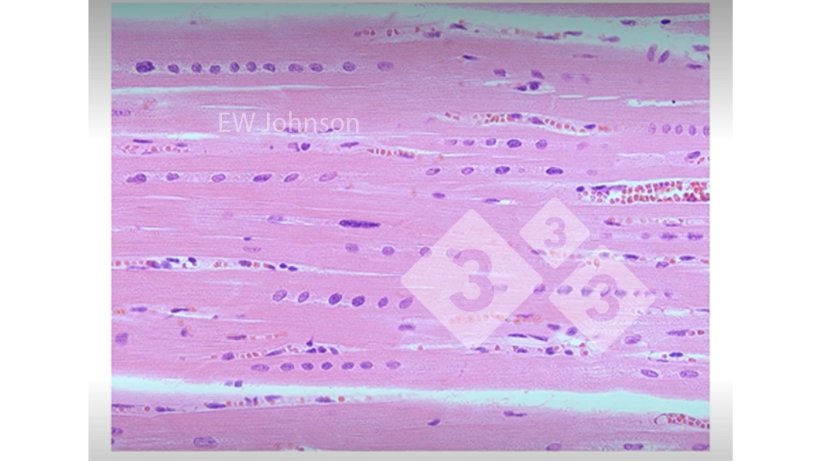

Parfois, nous pouvons trouver des choses que nous ne nous attendions pas à voir (figure 3).

Figure 3. Muscle cardiaque avec hémorragie, nécrose hyaline et alignement des noyaux montrant une carence en vitamine E et en sélénium. Ces porcs n'auraient pas un système immunitaire fonctionnant normalement.